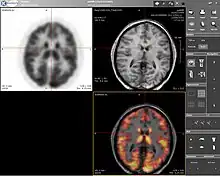

El sistema visual es la parte del sistema nervioso que brinda a los organismos el sentido de la vista. Este interpreta la información de la luz visible para construir una representación del mundo que rodea al cuerpo. El sistema visual tiene la compleja tarea de (re)construir un mundo tridimensional a partir de una proyección bidimensional del mismo. Nótese que las diferentes especies son capaces de ver diferentes partes del espectro de luz, por ejemplo, algunas pueden ver en el ultravioleta, mientras que otras pueden ver en el infrarrojo.